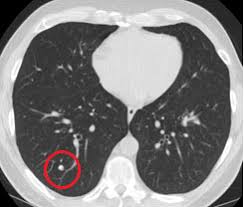

Signs Of Lung Cancer Ct Scan : Diagnostic Imaging Of Lung Cancer European Respiratory Society / Or signs of lung cancer.. The exact cause of lung cancer is still being investigated. Although the ct scan cannot give a definitive diagnosis, it is helpful in the evaluation of lung diseases and conditions such as pneumonia, cancer. The s sign of golden is seen when a collapsed upper lobe. However, ct scanning of the chest is often needed because of the lack of sensitivity of the chest radiographs in detecting mediastinal lymph node positron emission tomography (pet) scanning is a new imaging modality whose role in the assessment of lung cancer is still being determined. The most common signs of lung cancer are a cough that won't go away, chest pain, shortness of breath, weight loss, and fatigue.

If you do have these symptoms, see your doctor. Learn about lung cancer early warning signs, symptoms and treatments. Or signs of lung cancer. A tumor site located in the lung tissue or subpleural: Some lung cancers can be found by screening, but most lung cancers are your doctor will also examine you to look for signs of lung cancer or other health problems.

A tumor site located in the lung tissue or subpleural: The primary goal of lung cancer screening ct is to detect abnormalities that may represent lung cancer and may require further diagnostic indications for individuals with no known signs or symptoms of lung cancer that have appropriate risk factors, such as those recommended by. Changes in vesicular respirationpleural friction noise. Ct scan showing a cancerous tumor in the left lung. But mri scans use radio waves.